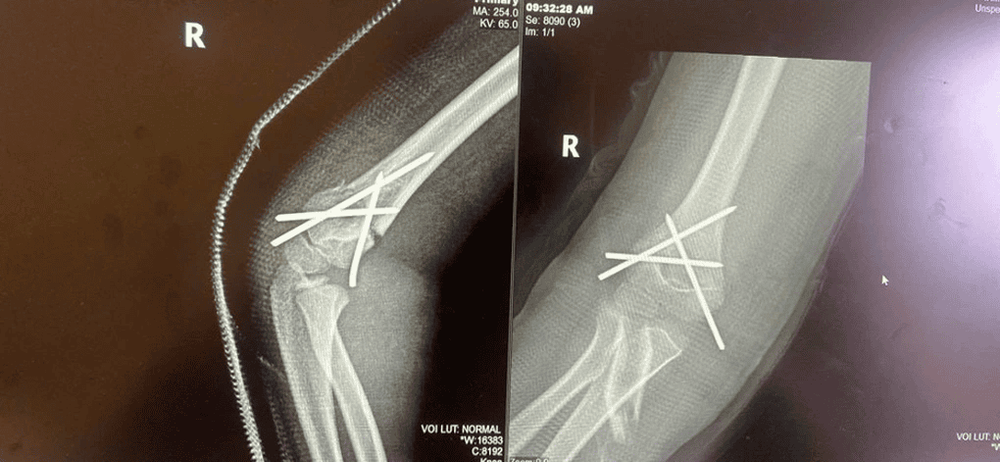

Tại đây, bệnh nhi được sơ cứu, giảm đau và cố định tạm thời khuỷu tay. Kết quả chụp X-quang cho thấy bé bị gãy trên lồi cầu xương cánh tay phải, di lệch nhiều. ThS.BSNT Vũ Đức Việt, khoa Ngoại Chấn thương chỉnh hình, cho biết nếu không điều trị kịp thời và đúng phương pháp, tổn thương này có thể để lại các di chứng như lệch khuỷu, cứng khớp hoặc tổn thương mạch máu - thần kinh.

Ca phẫu thuật được thực hiện dưới hướng dẫn của máy X-quang tăng sáng (C-arm). Bác sĩ tiến hành nắn chỉnh nhẹ nhàng đoạn xương gãy và sử dụng kim chuyên dụng để cố định ổ gãy. Phương pháp này có nhiều ưu điểm như: Hạn chế xâm lấn, mất máu rất ít, hạn chế sẹo mổ, giảm đau hiệu quả và rút ngắn thời gian hồi phục. Trẻ có thể vận động nhẹ sau 2 - 3 tuần và tháo kim sau khoảng 4 - 6 tuần.